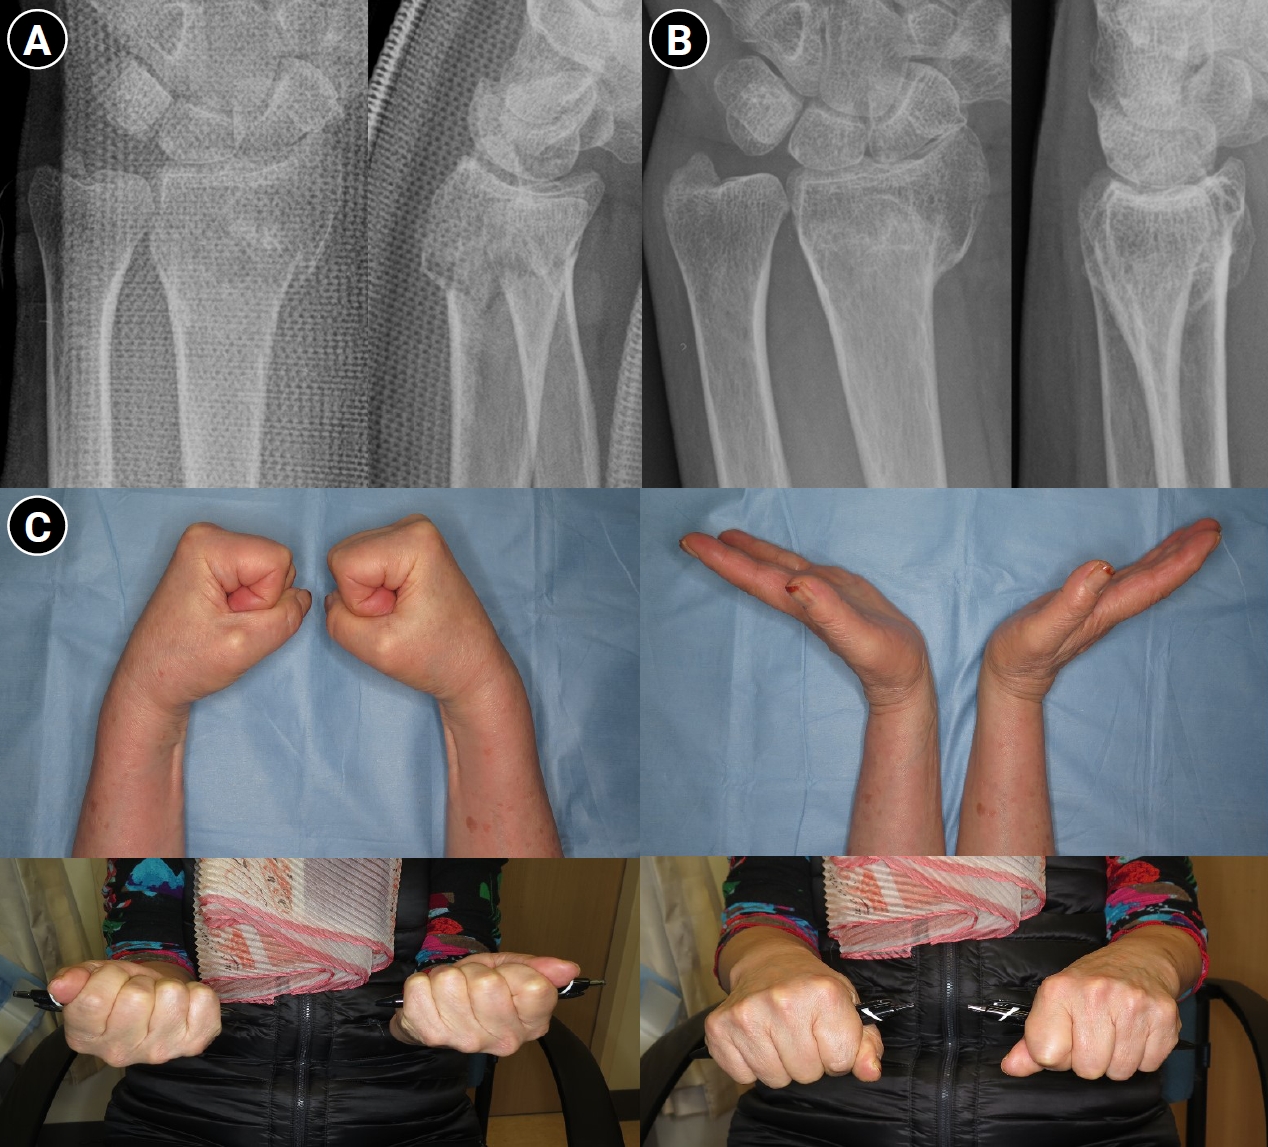

Fig. 1.

Successful conservative treatment of a displaced distal radius fracture in a 20-year-old female patient. (A) Immediate posttrauma wrist anteroposterior and lateral radiographs demonstrating a dorsally displaced intraarticular distal radius fracture of the right wrist. (B) Wrist radiographs obtained after manual reduction, showing restoration of volar tilt and radial length. (C) Wrist radiographs at 3 months posttrauma, demonstrating maintenance of fracture alignment and satisfactory fracture union.

Radiographic criteria for determining whether to proceed with operative treatment after successful reduction have also been extensively studied. With advances in surgical techniques and implants, operative treatment has shown improved outcomes, narrowing the indications for conservative management, especially in younger patients with high functional demands. Radial shortening of >2 mm, DRUJ subluxation, and significant anteroposterior translation of the distal ulna are generally considered unsuitable for conservative treatment. However, acceptable thresholds for intraarticular incongruity (<1 mm vs. <2 mm) and dorsal tilt (allowing up to 10° vs. allowing only neutral alignment) remain controversial (Fig. 1) [15-19]. Randomized controlled trials comparing conservative and operative treatment for displaced distal radius fractures have consistently demonstrated superior radiographic alignment following surgical fixation, particularly with respect to volar tilt and radial inclination at final follow-up [20]. Several studies have also reported modest advantages in early functional recovery and grip strength in surgically treated patients during the initial postoperative period [21,22]. However, long-term follow-up data in elderly populations indicate that these early advantages do not persist over time. Large prospective studies have shown that although volar locking plate fixation may facilitate faster early recovery, it does not confer superior patient-reported outcomes at 12 months when compared with cast immobilization [23,24]. In line with these findings, a comprehensive systematic review and meta-analysis by Gutierrez-Espinoza et al. [25] concluded that while statistically significant differences in radiologic and functional outcomes favor volar plate fixation, these differences do not exceed minimal clinically important difference thresholds. Furthermore, ulnar variance did not differ significantly between treatment groups, and radiographic parameters showed limited correlation with long-term clinical outcomes (Table 1) [20,22,24,26-28]. Collectively, these data suggest that despite the potential for radiographic malunion in conservatively managed cases, long-term functional recovery is not inferior to surgical intervention, supporting nonoperative management as a viable primary treatment option.